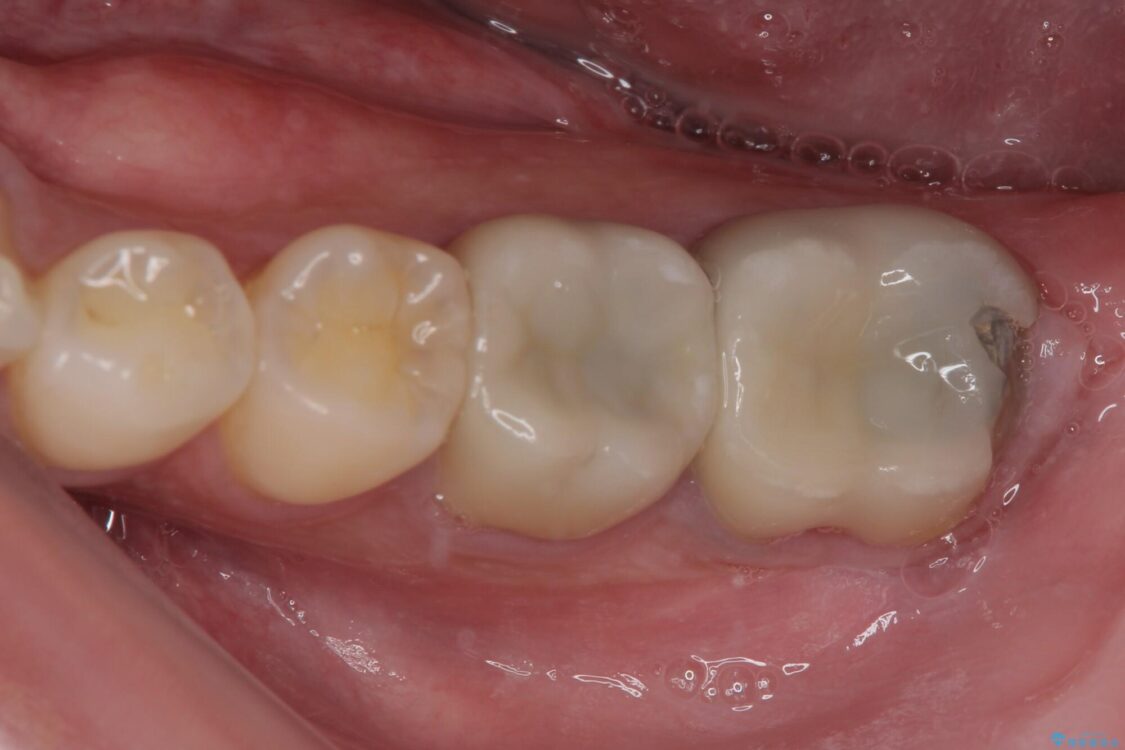

歯質の欠損が大きいため、処置後はオールセラミッククラウンにて補綴治療を行うこととしました。

後日状態を確認したところ、残された神経に異常は認められませんでした。

治療後

• 治療をしても違和感の続く奥歯 神経を極力残した虫歯治療 治療後画像